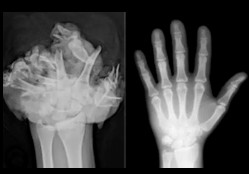

Stracić palce przez fajerwerki.

Stracić oko przez fajerwerki.

Mieć poparzoną połowę ciała przez fajerwerki.